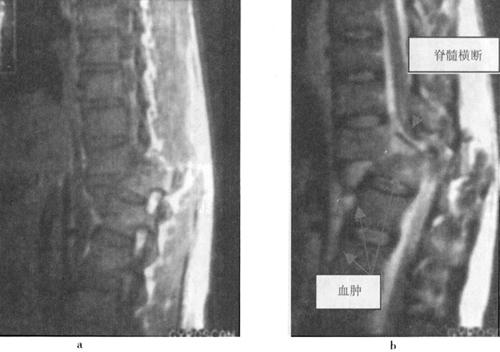

(2)出血:包括脊髓内出血和硬膜外血肿(图7-14至图7-16)、硬膜下出血和蛛网膜下腔出血等。脊髓内出血是不可逆损伤,其信号改变随时间变化较大。急性期(24h内)髓内出血灶在T1WI呈中等信号或不均匀信号,在T2WI呈中央低信号出血灶,外围水肿为高信号。亚急性期(3~5d)血肿在T1WI信号逐渐升高,在T2WI信号仍较低,慢性期血肿在T1WI和T2WI均为高信号。脊髓硬膜外血肿、硬膜下出血和蛛网膜下腔出血,在MRI上表现为椎管内脊髓外的软组织增厚影,在T1WI呈不均匀低信号,在T2WI为高信号。硬膜外出血脊髓受压移位明显。

图7-14 腰椎后柱骨折伴硬膜外出血,马尾受压。T1W(a)和T2W(b)矢状成像,椎管后方硬膜外可见T1W和T2W均为高信号的血肿

图7-17 T12压缩性骨折并脊髓横断性损伤:T1W(a)和T2W(b)矢状面扫描,可见T1压缩变扁,T11以上向前移位,脊髓呈横断性改变。椎间盘及脊柱前纵韧带下血肿。冠状面脊柱两侧亦见高信号出血

(5)脊髓横断:脊髓横断表现为脊髓和硬膜囊连续性中断,在矢状面显示清楚。完全性横断可伴有脊髓的回缩,两断端出现较宽的间隙。MRI检查T2WI较T1WI敏感,可清楚显示横断的脊髓,尤其是在T2WI,脑脊液呈高信号,而脊髓呈中等信号,两断端间充满高信号的脑脊液(图7-18)。不完全性脊髓横断,在T2W呈高信号,脊髓连续性尚存。

图7-18 T11椎体骨折脱位伴脊髓横断性损伤:T1W(a)和T2Wb矢状面示,T10以上明显向前脱位,椎管和脊髓在T11水平中断和成角,脊椎前、中、后柱骨折脱位,并有脊柱周围血肿